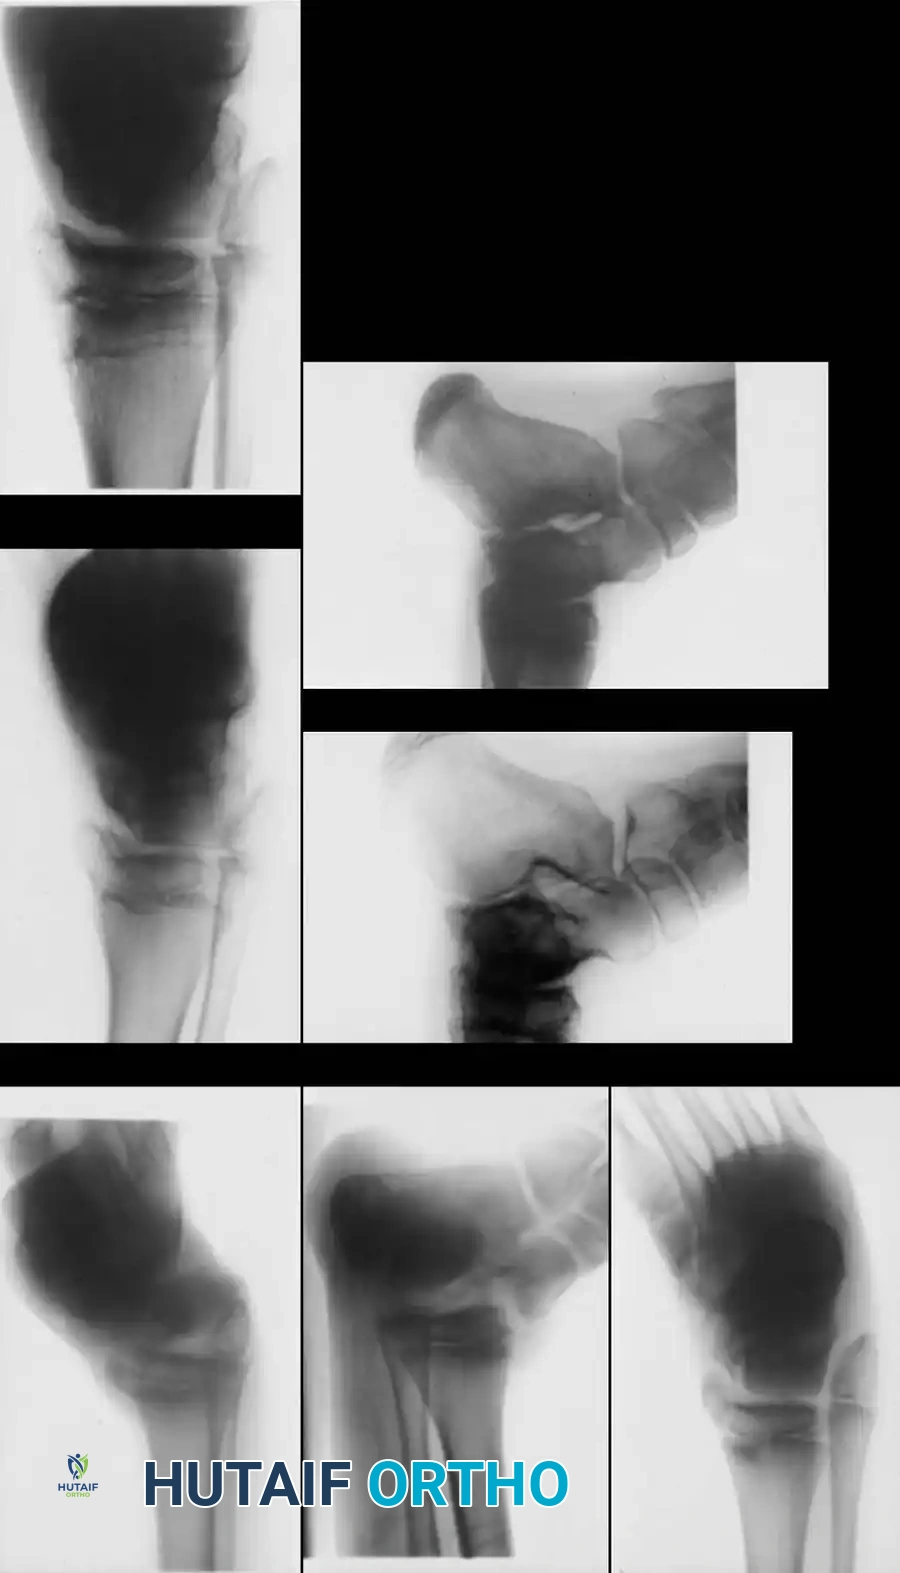

Pediatric Considerations in Talar Neck Fractures

Talar neck fractures in children behave differently than in adults. While osteonecrosis can still occur, the pediatric talus demonstrates a remarkable capacity for revascularization and remodeling. In our institutional evaluation of pediatric patients, those who developed osteonecrosis presented with a sclerotic lesion in the dome and body of the talus that subsequently became a cystic lesion on radiographs. Over a 2- to 3-year period, the area resolved, and the vast majority remained asymptomatic at long-term follow-up.

Fig. 33-202 A and B, Type III talar neck fracture with posteromedial displacement in 9-year-old child. C, After closed reduction and cast immobilization. D and E, At 9 months after injury, there is evidence of healing, but osteonecrosis of talus with sclerotic and cystic changes is evident. F and G, At 6 years after injury, physes are still open, and some healing of osteonecrosis of talus has occurred; patient has no symptoms.

Most children with osteonecrosis do not require surgery. A prolonged period of non–weight bearing or the use of a patellar tendon–bearing, weight-relieving brace should be strictly trialed before any surgical intervention is considered.

Pediatric talar healing progression demonstrating gradual resolution of cystic changes over time with conservative bracing.